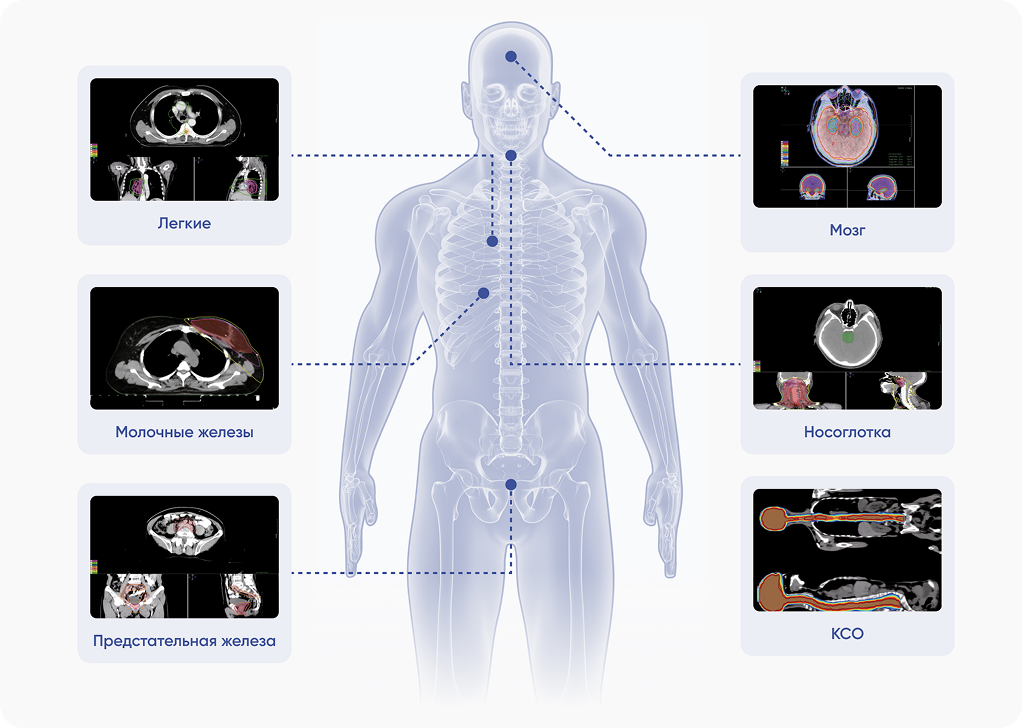

Лечение опухолей любой локализации

Система планирования лучевой терапии

Система планирования лечения TiGRT TPS с аппаратным ускорением (GPU) использует алгоритм Монте-Карло для быстрого расчета дозы терапевтического облучения. Поддерживает все виды лучевой терапии: 3D-CRT, IMRT, VMAT и SRS/SBRT.

| Методики лучевой терапии | 3D-CRT , IMRT , IGRT , VMAT , SRS , SBRT |

| Система трехмерного дозиметрического планирования лучевой терапии | TiGRT TPS |